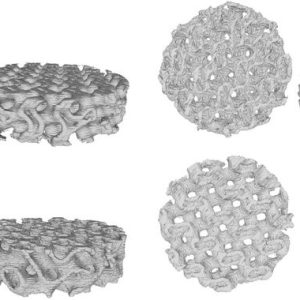

مطالعه کشت سلولی استاتیک و دینامیک برونتنی داربستهای استخوانی جدید بر پایه PLA چاپ شده به روش سه بعدی و هیدروژل آلژینات مملو از سلول

نویسندگان: رضا نورزی، محمد امین شامخی، رضا محمودی، علی ذوالفقاریان، فاطمه اصغری، علی موسویزاده، محمد بداغی، امین هادی و نوشین حقیقیپور چکیده:هدف این مقاله طراحی